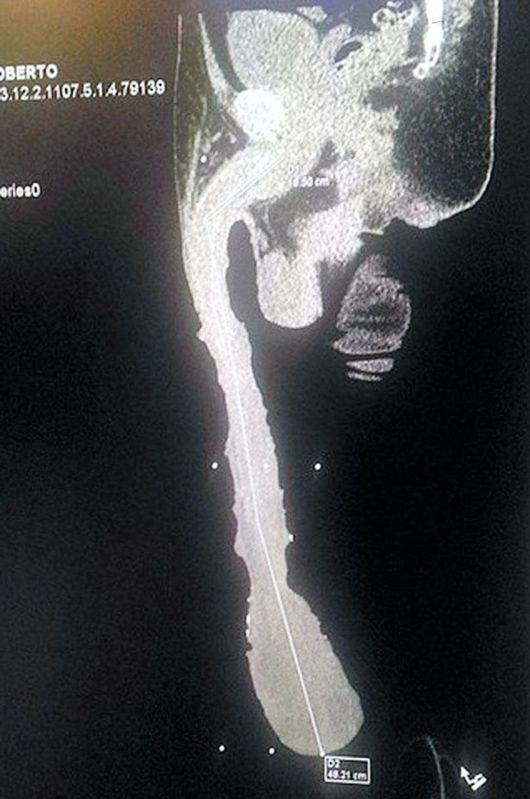

영국 일간지 '미러'는 5일(현지시간) 세상에서 가장 긴 성기를 가진 남성의 사연을 소개했다. 주인공은 멕시코의 로베르토 에스퀴벨 카브레라(52)라는 남성. 이 매체에 따르면 카브레라는 길이 18.9인치(약 48cm), 무게 2.2파운드(약 998g)의 거대한 성기를 보유하고 있다.

안타깝게도 이 남성은 여성들이 두려워해 성관계를 갖지도 못하며 주위에 친구도 없는 것으로 알려졌다. 또한 사회 지원을 통해 생계를 어렵게 이어가고 있어 안타까움을 자아내고 있다. /OSEN<사진> 미러 홈페이지 캡처.